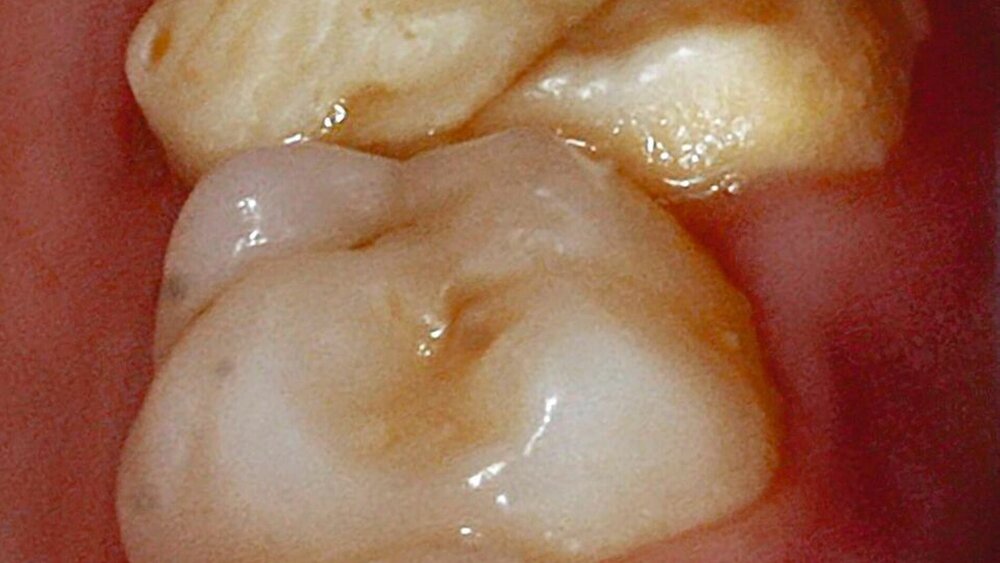

Mit 514 von 517 hatten fast alle Befragten bereits Patienten mit MIH behandelt, und 92,5 Prozent betrachteten MIH als ein bedeutendes klinisches Problem. Häufig wurden klinisch gelb-braune Defekte (81 Prozent), Schmelzverlust (46 Prozent) und weiße Defekte (36,4 Prozent) beobachtet. Gut zwei Drittel der Befragten (68,6 Prozent) stellten eine Zunahme der MIH-Prävalenz im Verlauf ihrer Berufstätigkeit fest, 20,7 Prozent waren sich unsicher und nur rund jeder zehnte Befragte (10,7 Prozent) sah keine Zunahme der Prävalenz. Die Zahnärzte gaben als Probleme bei der Behandlung der MIH das Verhalten des Kindes (44,7 Prozent), Schwierigkeiten mit der Lokalanästhesie (22,7 Prozent) und eine verlängerte Behandlungsdauer (15,3 Prozent) an.